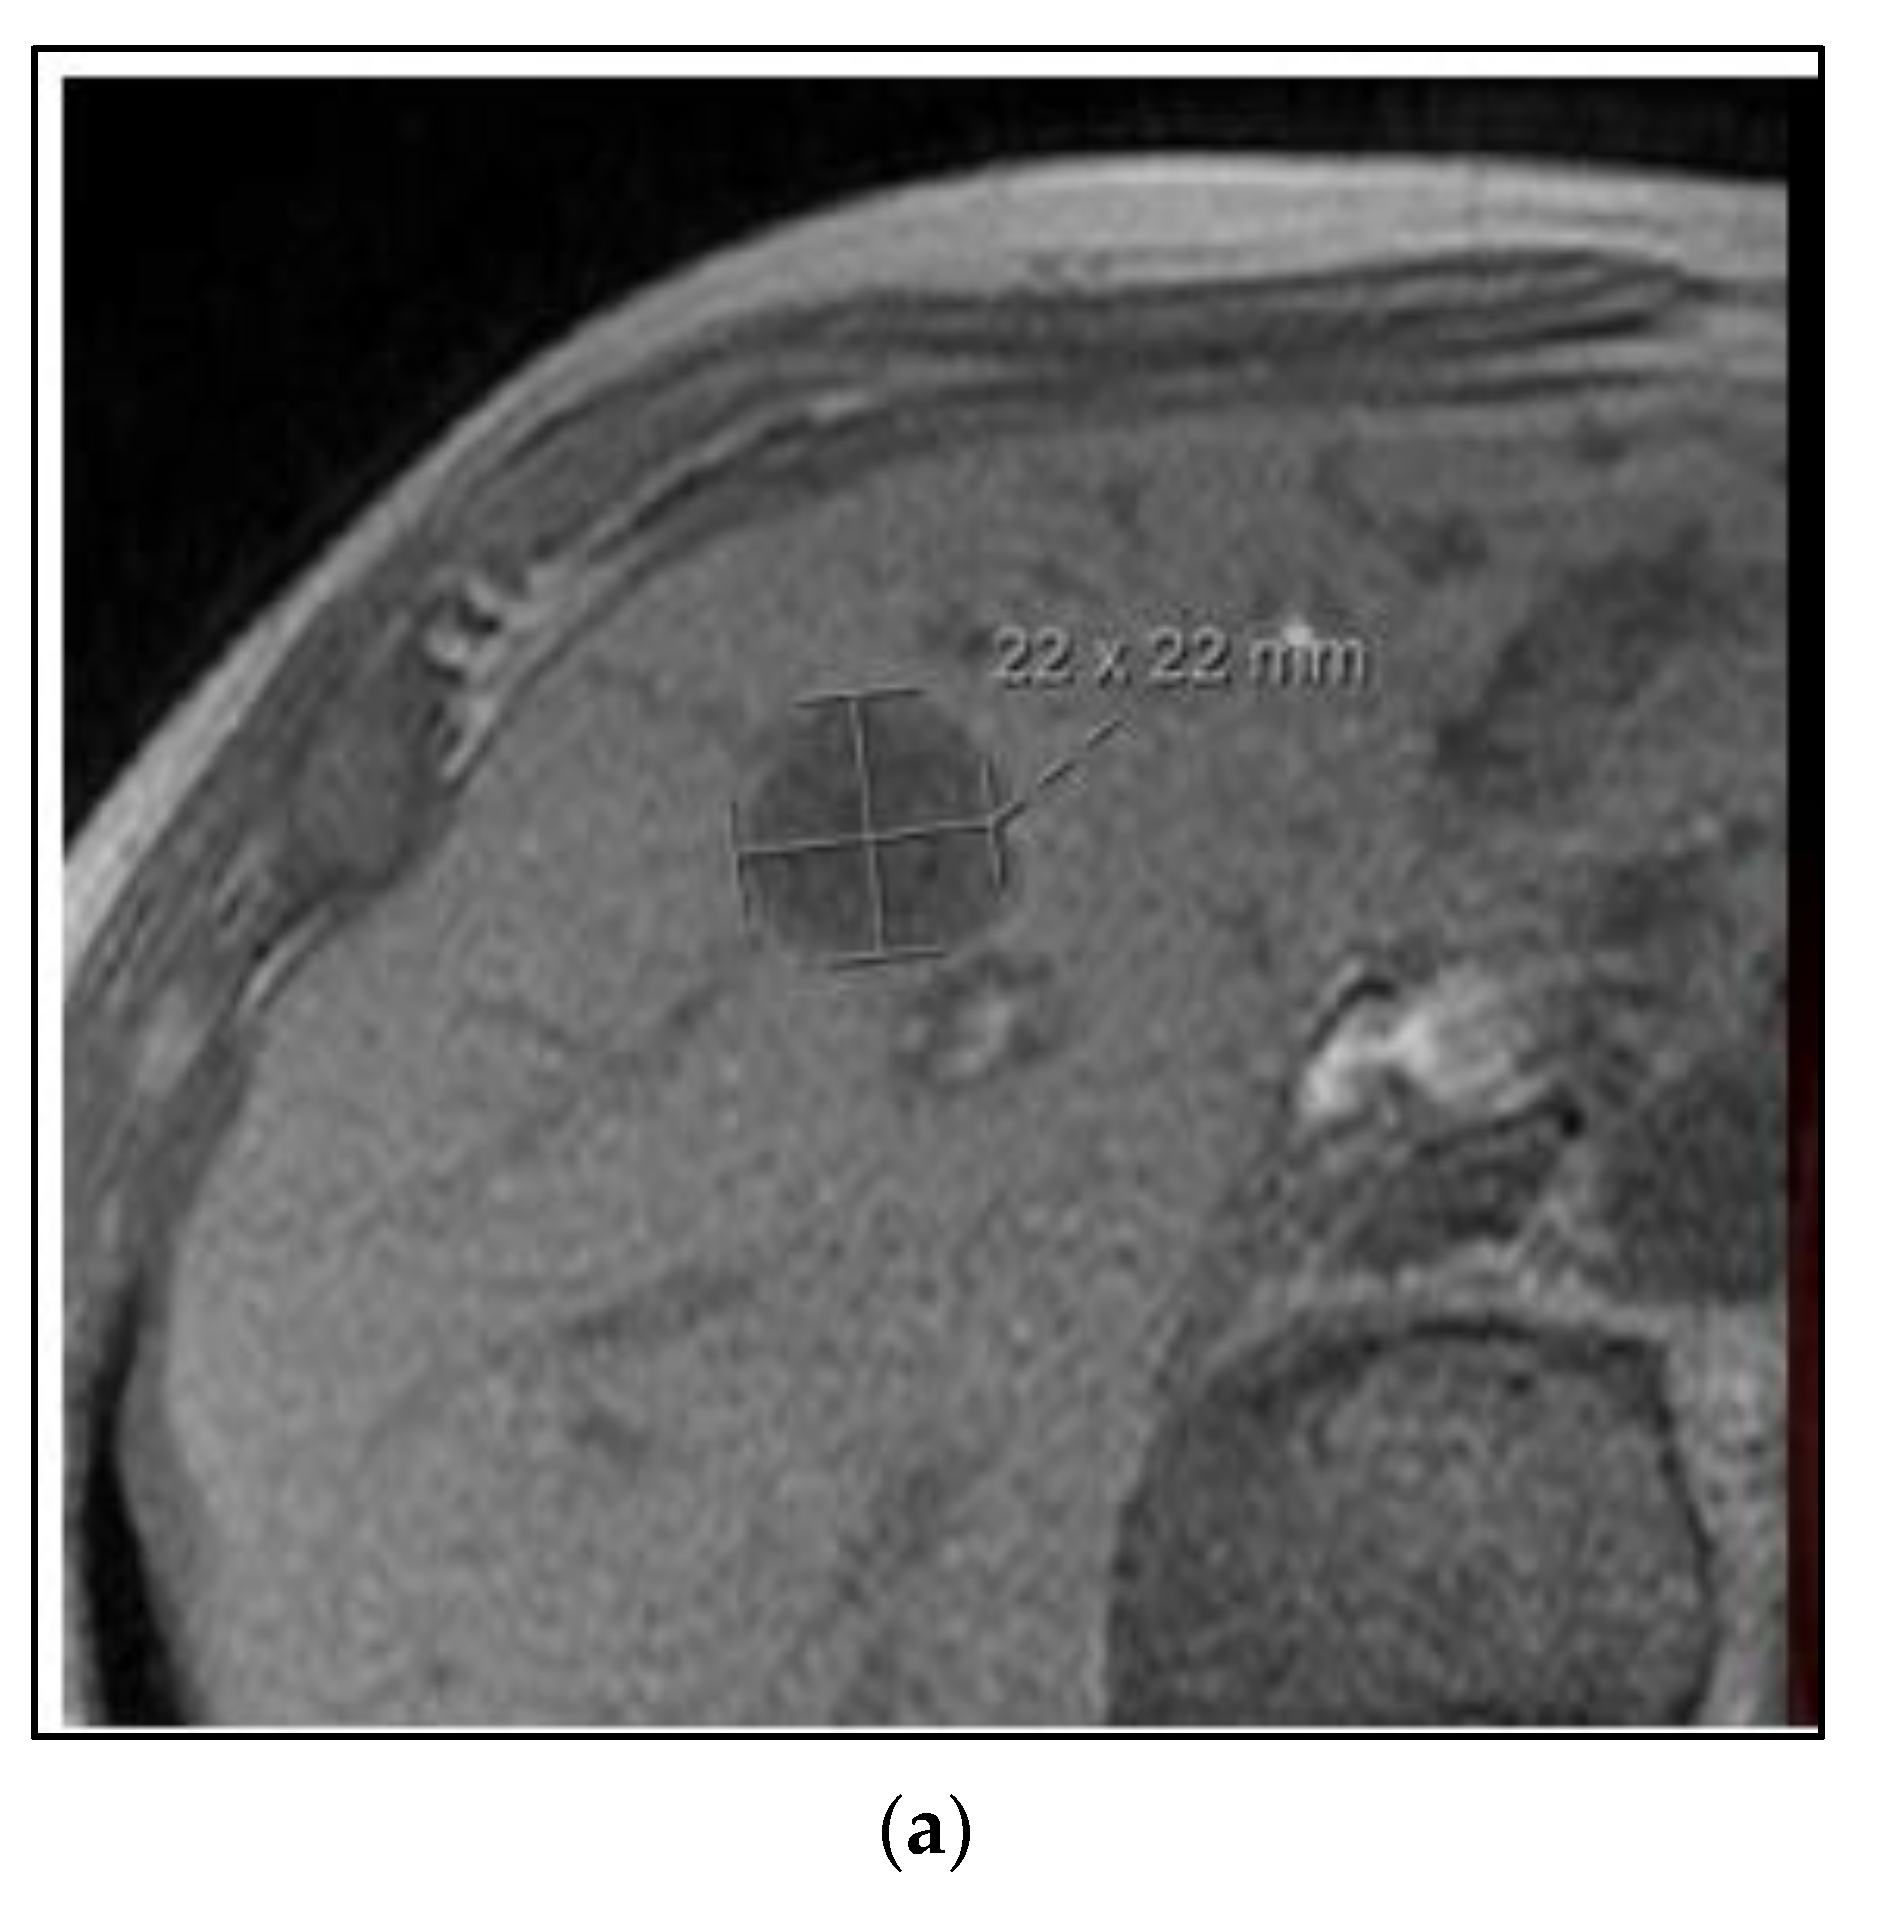

The majority of the patients in the BR002 trial had metachronous oligometastases after the initial local-regional treatment. Figure 4 shows a case of a 75-year-old woman with a metachronous presentation of oligometastatic breast cancer to the liver. Her initial node positive breast cancer was ER positive, PR positive, and HER2 negative and treated more than five years earlier with mastectomy, postmastectomy radiation, chemotherapy and five years of tamoxifen. She developed abdominal symptoms and elevated liver function tests and imaging showed two lesions of the liver, 2.2 cm and 0.8 cm. A liver biopsy was positive for metastatic breast cancer of the same receptor pattern as the original primary. She was treated with SBRT to both liver lesions, followed by an aromatase inhibitor and remains without evidence of disease progression four years later.

Figure 4. Case 3: Metachronous oligometastases. A 75-year-old woman presented with metachronous metastatic breast cancer to the liver over 5 years from her initial treatment. She was treated with SBRT to both liver lesions. MRI (a) and PET/CT (b) imaging of one of the two liver metastases. (c) A colorwash image superimposed on a radiation planning CT showing the dose from SBRT to 50 Gy in 5 fractions using proton beam radiation. Representative images showing a complete response on MRI (d) and PET/CT (e) 4 years after SBRT treatment.